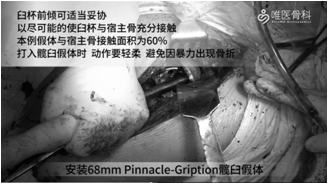

安装髋臼假体:给予脉冲冲洗后,依次进行68mm Pinnacle-Gription髋臼假体的安装、钻孔、拧入螺钉和安装聚乙烯衬垫。

注意:①臼杯前倾可适当妥协,以尽可能使臼杯与宿主骨充分接触,本病例假体与宿主骨接触面积为60%。②打入髋臼假体时,动作要轻柔,避免因暴力出现骨折。③螺钉固定时,尽量使用多个螺钉将髋臼杯固定到宿主骨上以提供整个结构的稳定性。